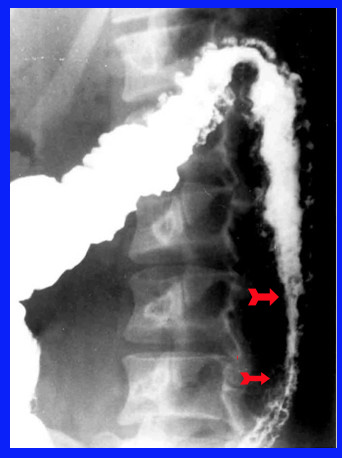

- חוקן בריום: ניתן לראות היעלמות של האוסטרציות, חוסר סדירות, כיבים קטנים, היצרויות ולפעמים תבנית פוליפואידית של הרירית (תצלום 32.6). בדלקת כיבית של הכרכשת ניתן לראות הרחבה של המרווח בין החלחולת לעצם העצה (Sacrorectal space גדול מ- 1 ס"מ).